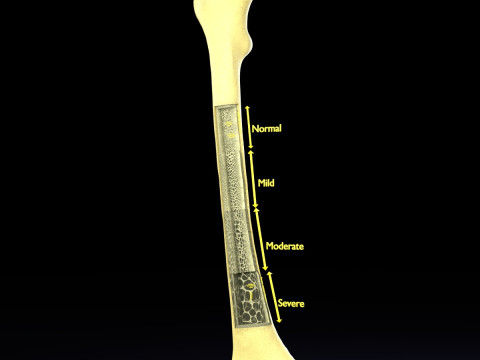

The model meshes include adult circulation versus circulation in Tetralogy of Fallot (TAF), arrow labels and text labels. The blood flow in a patient with Tetralogy of Fallot is outlined in this model. To contrast it to normal blood circulation a separate model of normal circulation is included. The Tetralogy of Fallot (OVER RIDING OF AORTA, PUL STENOSIS, VENTRICULAR SEPTAL DEFECT, RIGHT VENTRICULAR HYPERTROPHY), fossa, ligament teres , venosus, and arteriosus are duly depicted with proper labelling and blood flow directional arrows. Excellent model for teaching, demonstration and knowlegde of human body. The models include both procedural and image textures blend files separately. The texture file include diffuse, roughness and normal png and jpeg based on non overlapping UV maps.